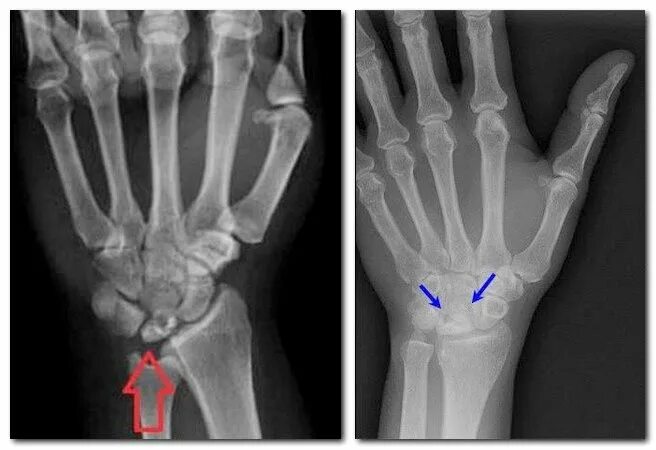

Перелом лучезапястного сустава мкб 10